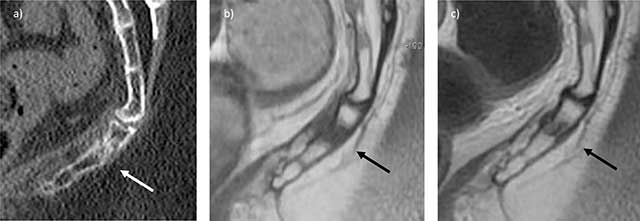

Figure 7

Stress fracture of the coccyx in the immediate postpartum. Sagittal CT view a) and T1 b) and T2 c) MRI views show the fracture line (arrow) associated with adjacent bone and soft tissue edema (courtesy Dr M. Kasbi).